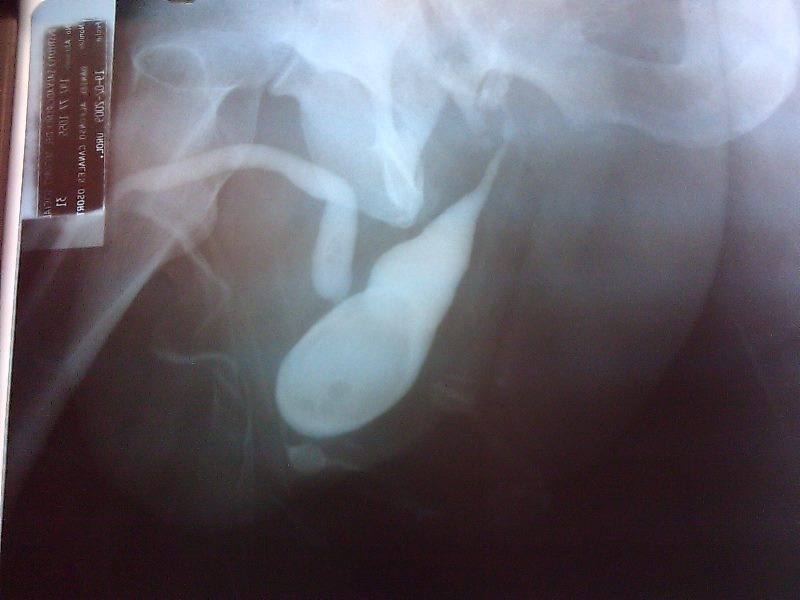

Reparo divertículo uretral

Envíado por Dr. Juan Carlos Iglesias Guzmán